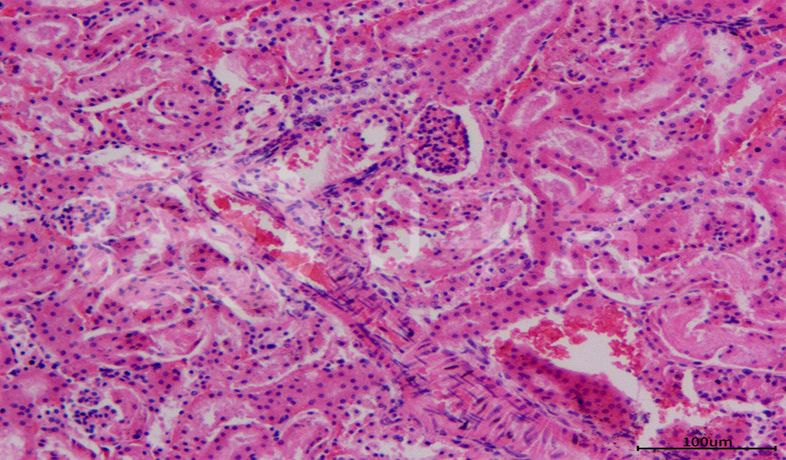

病理平臺(tái)可承接:石蠟切片,切片掃描,熒光掃描,HE染色,各種特殊染色,如:Masson、油紅O、PAS、番紅O、ALP、TRAP、甲苯胺藍(lán)以及免疫組化/熒光、原位雜交等,3D HISTECH滿足對(duì)結(jié)果高質(zhì)量,高標(biāo)準(zhǔn),周期快的實(shí)驗(yàn)外包需求,并提供染色培訓(xùn)服務(wù),分線上視頻,線下實(shí)操帶教兩種培訓(xùn)方案。

案例展示

組織染色實(shí)驗(yàn)室